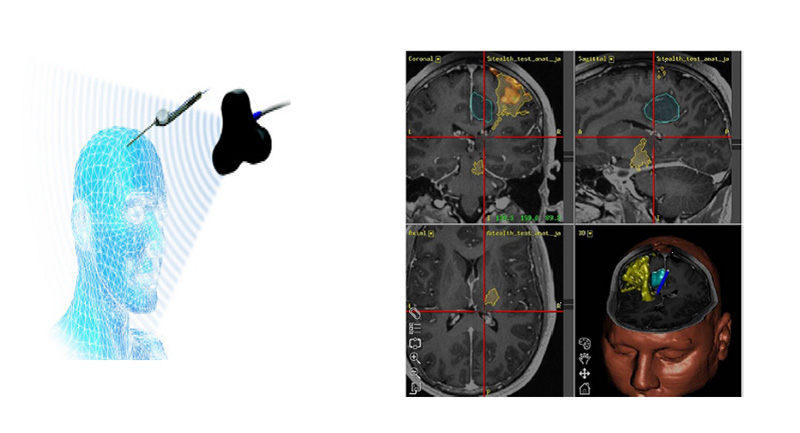

Η σύγχρονη τεχνολογία χειρουργικής πλοήγησης έχει συμβάλει σημαντικά στην πρόοδο της Νευροχειρουργικής και έχει καθιερωθεί διεθνώς ως η μέθοδος εκλογής στις επεμβάσεις κρανίου, αντικαθιστώντας τις παλαιότερες στερεοτακτικές μεθόδους με χρήση πλαισίου.

Οι βασικές εφαρμογές στη νευροχειρουργική είναι:

- Αφαίρεση όγκων εγκεφάλου και νωτιαίου μυελού. (Επιλογή κρανιοτομίας, πορείας προσέγγισης και χειρουργικής προσπέλασης, εντοπισμός και οριοθέτηση όγκου)

- Βιοψία και τοποθέτηση καθετήρων

- Λειτουργική Νευροχειρουργική (τοποθέτηση ηλεκτροδίων για εν τω βάθει εγκεφαλική διέγερση)

- Χειρουργική σπονδυλικής στήλης

Η χρήση χειρουργικής πλοήγησης αναπτύσσεται ταχέως τα τελευταία χρόνια στις επεμβάσεις σπονδυλικής στήλης, καθώς παρέχει τρισδιάστατη απεικόνιση των ανατομιών διεγχειρητικά και επιτρέπει, παράλληλα, τον εντοπισμό της ακριβούς θέσης των εργαλείων και εμφυτεύσιμων υλικών (βίδες) σε σχέση με τη συγκεκριμένη ανατομία. Επιτρέπει, συνεπώς, το λεπτομερή σχεδιασμό της χειρουργικής προσπέλασης, καθώς και την απεικόνιση της προσπέλασης των βιδών σε πραγματικό χρόνο.